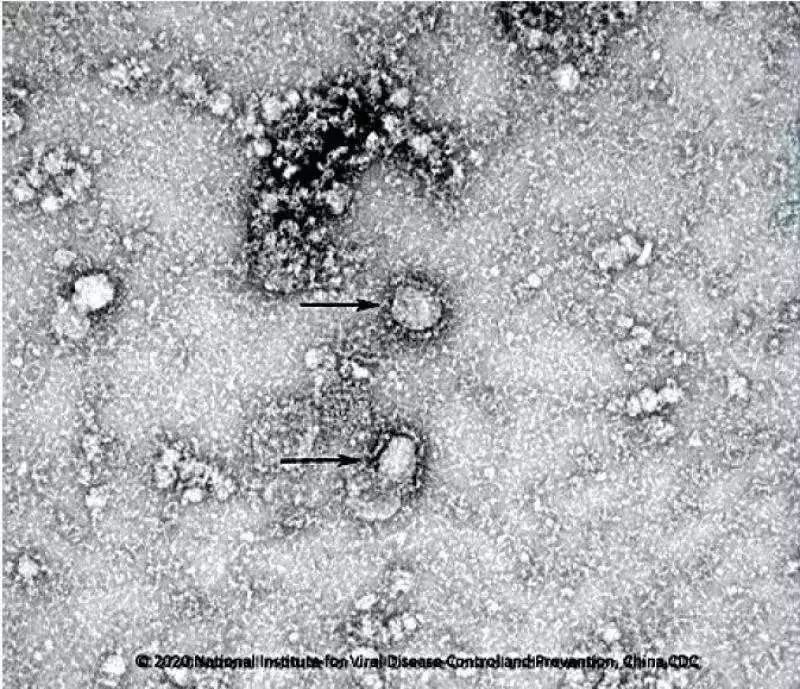

Electron microscopic images of the first strain of the novel coronavirus released by the Chinese Center for Disease Control and Prevention on Jan. 24, 2020 (Chinese Center for Disease Control and Prevention/Xinhua)

The website of the service system is http://nmdc.cn/#/nCoV. Electron microscopic images of the virus, primers and probes for virus detection are also available on the site.